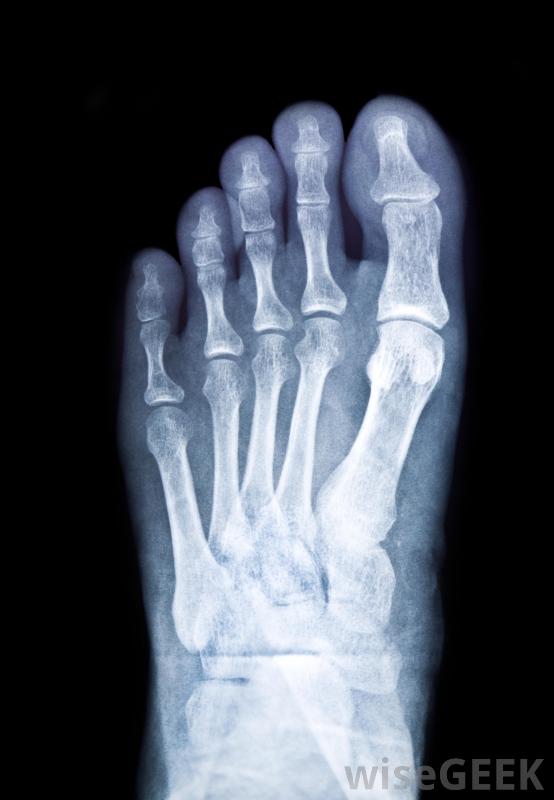

保持水分有助于防止足部抽筋脚上的肌肉拉伤或是摔伤很常见,可能是因为脚受伤或摔伤造成的,如果脚部没有骨折,最好的治疗方法是抬起脚,敷上冰袋,让伤口愈合。如果脚痛在短时间内没有改善,最好去看医生照个x光片,看看是否真的断了皮不合适的鞋子是导致脚痛的另一个最常见的原因尤其是足弓较低或特别高的人,需要更多的支撑。鞋跟或鞋子太平,既会使脚趾抽筋,又会使足弓伸展,从而导致肌腱炎或足底筋膜炎,这两种鞋都很痛苦。选择能为脚提供更好的缓冲和支撑的鞋子,同时允许脚趾有活动空间,是一个不错的选择。稳定性或运动控制鞋通常是支撑非常高的足弓的最佳选择,而鞋垫较低的鞋可能是相对平足的人的更好选择

如果脚伤在短时间内没有好转,则应拍一张x光片看看脚是否骨折其他足部疾病,如内生脚趾甲、足底疣、脚癣、痛风或囊肿等,也会导致脚部疼痛。通常可以通过将脚趾甲横切、不要太短、也不要磨圆边缘来防止脚趾甲向内生长。此外,疣有时可以在家里用去疣剂治疗,这种药可以在商店里买到。其他情况可能需要足疗医生治疗,以帮助减轻疼痛或防止病情恶化;有些情况实际上可能需要手术痛风是脚痛的常见原因足底疣是足部疼痛的常见来源